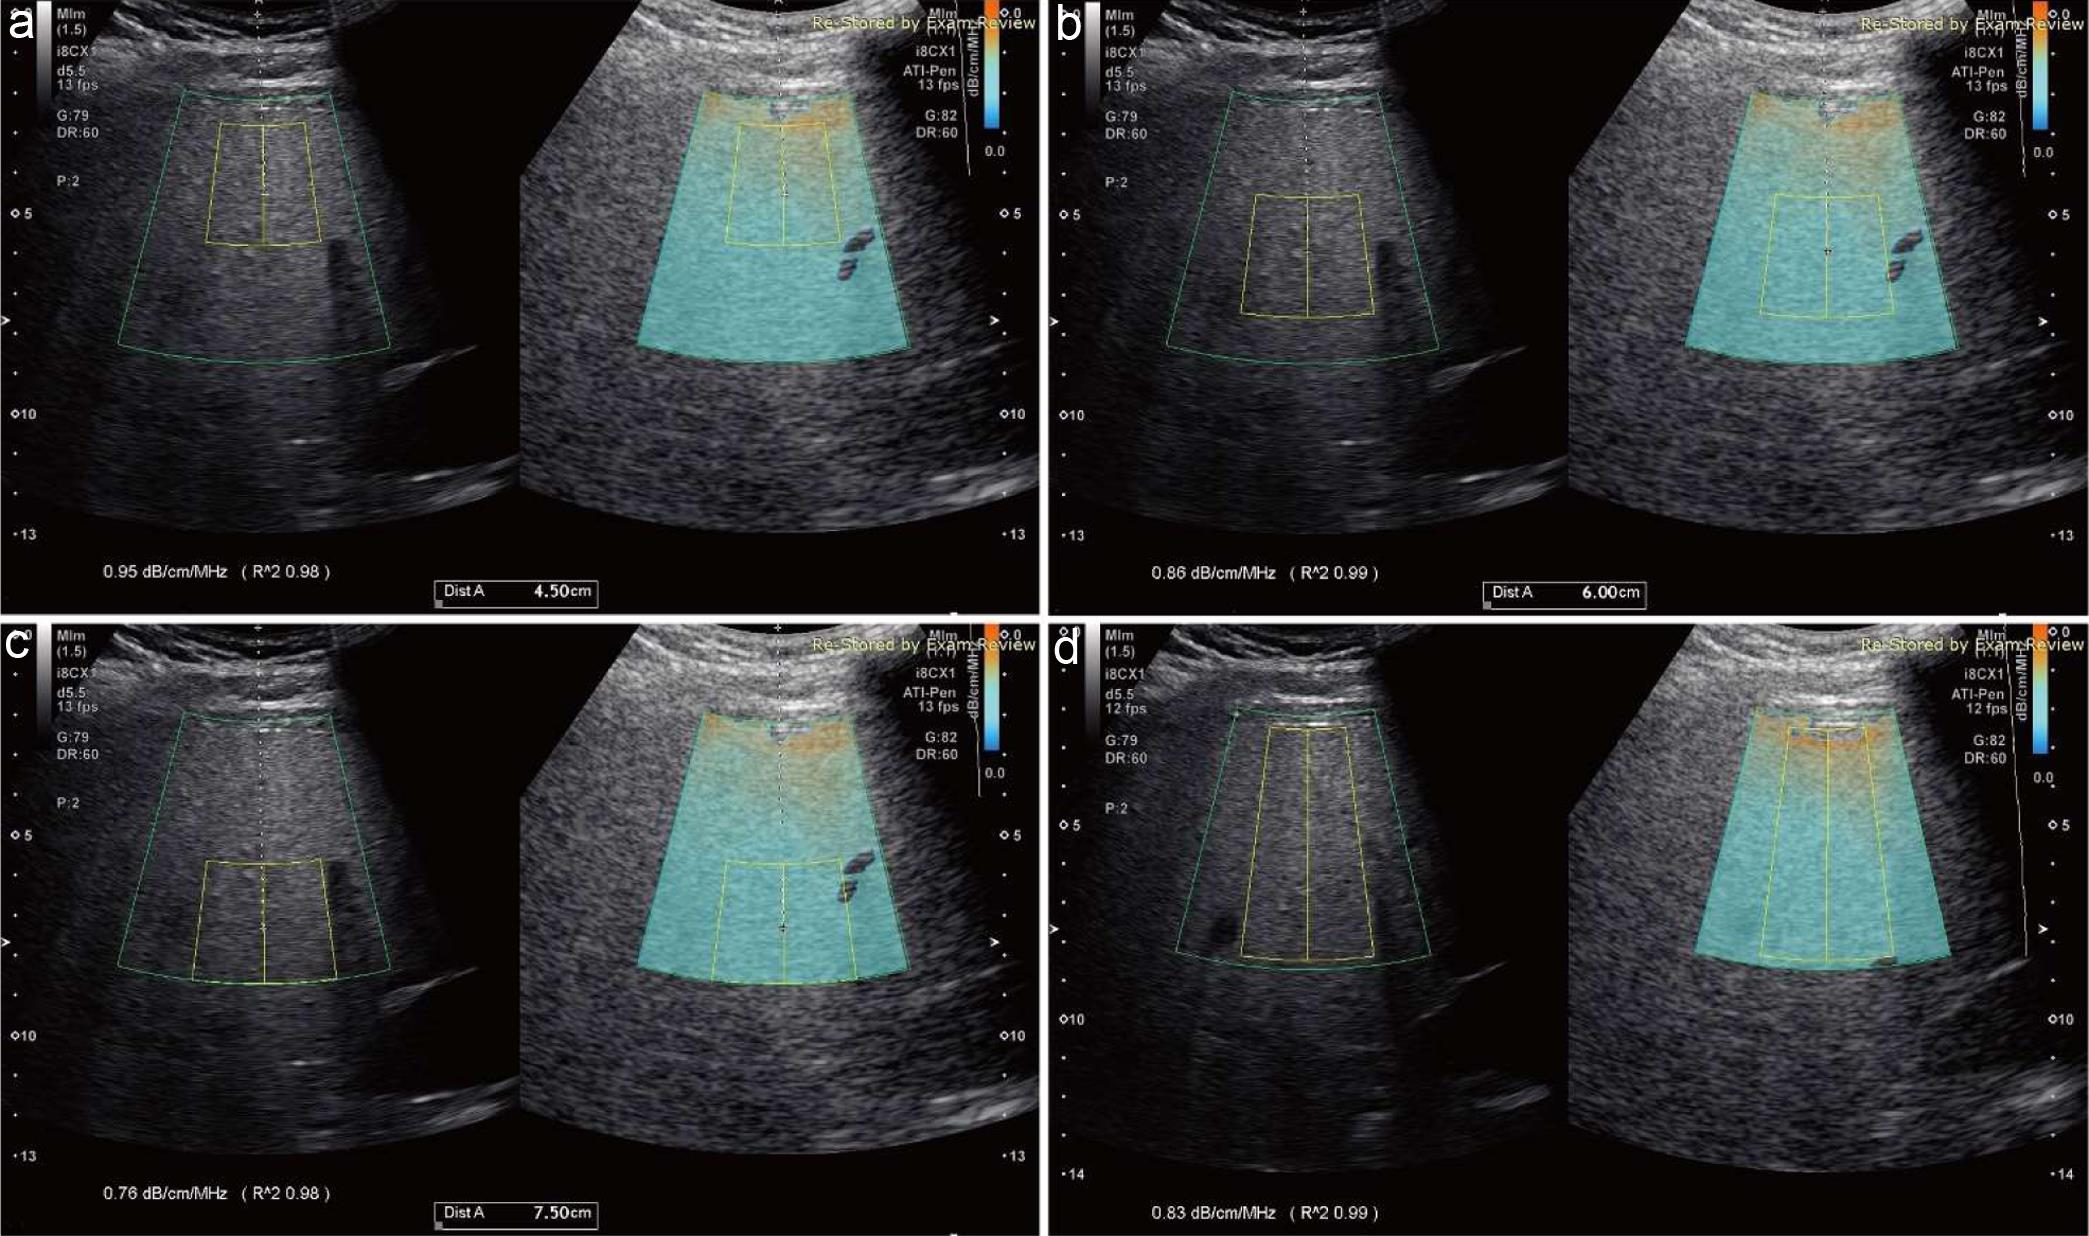

Technical errors in measuring liver attenuation coefficient (AC).

Fig. 4  Technical errors in measuring liver attenuation coefficient (AC).

Common technical errors in performing liver ultrasound attenuation imaging (ATI) are dark orange area (white arrow, a), the liver capsule (b), the region with blank color at the depth of >10 cm (c, the white arrow points R2 < 0.90), and acoustic shadowing (white arrows, d) included in the measurement ROI. In addition, placing measurement ROI out of the center of the ultrasound attenuation imaging (ATI) image and/or sound beam (white arrow) to liver capsule (yellow solid line) off 90 degrees (e) may also maximize scattering sound energy to various directions resulting in measurement errors.

In the study, the best ROI depth for measuring liver AC is at 6 cm from the skin (Fig. 1b) resulting in the highest diagnostic performance of AC to determine ≥ mild hepatic steatosis, ATI quality, and lowest failure rate compared with AC values measured at depths of 4.5 cm, 7.5 cm, and large ROI. The ROI depth at 4.5 cm seemed to be too close to the liver capsule to avoid the dark orange color area produced by high noise or reverberation artifact (Fig. 4a, b) in some patients. The ROI depth at 7.5 cm was often too deep from the skin to exclude the dark blue area (weak echo signal, Fig. 4c) due to less sound penetration,19 which yielded the poor ATI quality, low diagnostic performance, and high failure rate. The utilization of a large ROI is able to assess tissue attenuation in relative larger region of liver parenchyma (6.5 cm × 7.3 cm vs. 3 cm × 3 cm). However, using a large ROI to measure liver AC magnifies technical challenges to place such a large ROI in a small liver (such as a cirrhotic liver) and avoid prominent hepatic vessels (e.g. dilatation of the hepatic veins in congestive heart failure or portal vein in significant portal hypertension). Further, AC measured at the depth of 7.5 failed to distinguish steatotic livers from normal livers as the difference in AC value between normal and steatotic livers was not significant (p = 0.10, Table 1).

• The region below the liver capsule appearing dark orange color on ATI is produced by ultrasound reverberation artifact (Fig. 4a). Therefore, dark-orange color below the liver capsule should be excluded from ROI for measuring liver AC.22

• The liver capsule should be excluded from the measurement ROI (Fig. 4b).

• The posterior region with dark blue (Fig. 4c) or blank color should be avoided from measurement ROI.23

• Acoustic shadowing behind the ribs and/or lung (Fig. 4d) should be avoided from the measurement ROI.

• The propagation direction of the ultrasound beam is not perpendicular to the liver capsule. Angling of the liver capsule (Fig. 4e) may cause stronger sound beam reflection and refraction once the angle between sound beam and the liver capsule is off 90 degrees, which may affect AC estimation.